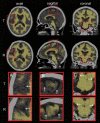

Brain atrophy is correlated with risk of cognitive impairment, functional decline, and dementia. Despite a high infectious disease burden, Tsimane forager-horticulturists of Bolivia have the lowest prevalence of coronary atherosclerosis of any studied population and present few cardiovascular disease (CVD) risk factors despite a high burden of infections and therefore inflammation. This study (a) examines the statistical association between brain volume (BV) and age for Tsimane and (b) compares this association to that of 3 industrialized populations in the United States and Europe. This cohort-based panel study enrolled 746 participants aged 40-94 (396 males), from whom computed tomography (CT) head scans were acquired. BV and intracranial volume (ICV) were calculated from automatic head CT segmentations. The linear regression coefficient estimate β^T of the Tsimane (T), describing the relationship between age (predictor) and BV (response, as a percentage of ICV), was calculated for the pooled sample (including both sexes) and for each sex. β^T was compared to the corresponding regression coefficient estimate β^R of samples from the industrialized reference (R) countries. For all comparisons, the null hypothesis β T = β R was rejected both for the combined samples of males and females, as well as separately for each sex. Our results indicate that the Tsimane exhibit a significantly slower decrease in BV with age than populations in the United States and Europe. Such reduced rates of BV decrease, together with a subsistence lifestyle and low CVD risk, may protect brain health despite considerable chronic inflammation related to infectious burden.